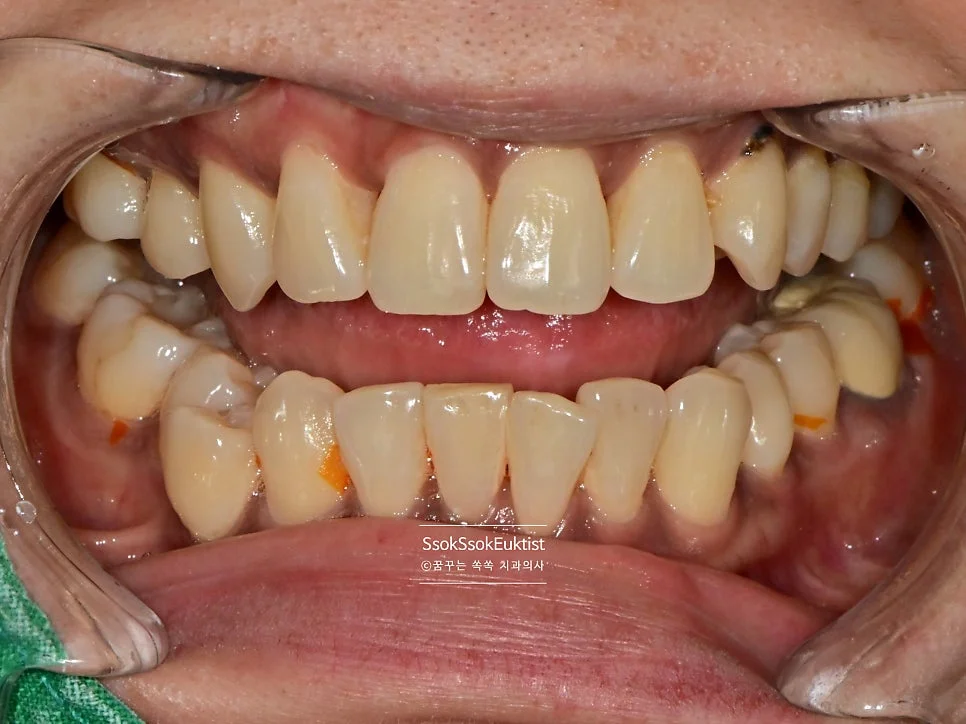

Case 3. 검은 착색 — 분사형 스케일러로 해결

착색 제거 케이스3 전 검은 착색

치아 표면의 검은색 착색 — 제거가 안된다며 찾아오신 분

치아 표면에 검은색 착색이 제거가 안된다며 찾아오신 분인데요. 분사형 스케일러를 이용해 스케일링뿐만 아니라 착색물질도 깨끗하게 제거해 봅니다!^^

착색 제거 케이스3 후 깨끗한 치아

검은 착색 제거 후 깨끗해진 치아 정면

착색 제거를 하기 위해서는 가루를 강한 수압으로 분사하는 분사형 스케일러가 필수입니다^^